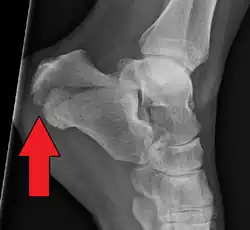

Fratura da parte posterior do calcâneo.

Fratura do calcâneo é uma lesão do osso do calcanhar, geralmente por caída de altura ou acidente automobilístico. Os sintomas podem incluir dor, tumefação, hematomas, dificuldade para andar e deformidade do calcanhar. Representa 2% de todas as fraturas, mas 60% das fraturas de tarsos. Frequentemente está associado a outras fracturas do pé, tornozelo, joelho, quadril ou das costas.[1]

A suspeita surge no exame físico e é confirmada com radiografias convencionais ou com tomografia. Radiografia convencional é geralmente a ferramenta de avaliação inicial quando se suspeita de uma fratura do calcâneo. As radiografias recomendadas são (a) axial, (b) anteroposterior, (c) oblíqua e (d) com flexão dorsal e rotação interna do pé. Entretanto, a radiografia convencional é limitada para visualização da anatomia do calcâneo, especialmente na articulação subtalar, que é melhor visualizada com uma tomografia.[2]

O Ângulo de Gissane, ou "Ângulo Crítico", é o ângulo formado pelas encostas descendente e ascendente da superfície superior do calcâneo. Em uma radiografia lateral, um ângulo de Gissane> 130 ° sugere fratura da superfície da articulação subtalar posterior. O ângulo de Bohler, ou o "Tuber Angle", é outro marco anatômico normal visto nas radiografias laterais. É formado pela intersecção de 1) uma linha desde o ponto mais alto da faceta articular posterior até o ponto mais alto da tuberosidade posterior, e 2) uma linha a partir do primeiro até o ponto mais alto da faceta articular anterior. O ângulo de Bohler é normalmente de 25 ° a 40 °. Um ângulo diminuído é indicativo de uma fratura do calcâneo.[3]